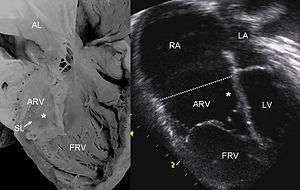

| Pathological specimen and ultrasound image of a heart with Ebstein's anomaly: Abbreviations: RA: right atrium; ARV: atrialized right ventricle; FRV: fight ventricle; AL: anterior leaflet; SL: septal leaflet; LA: left atrium; LV: left ventricle; asterisk: grade II tethering of the tricuspid septal leaflet | |